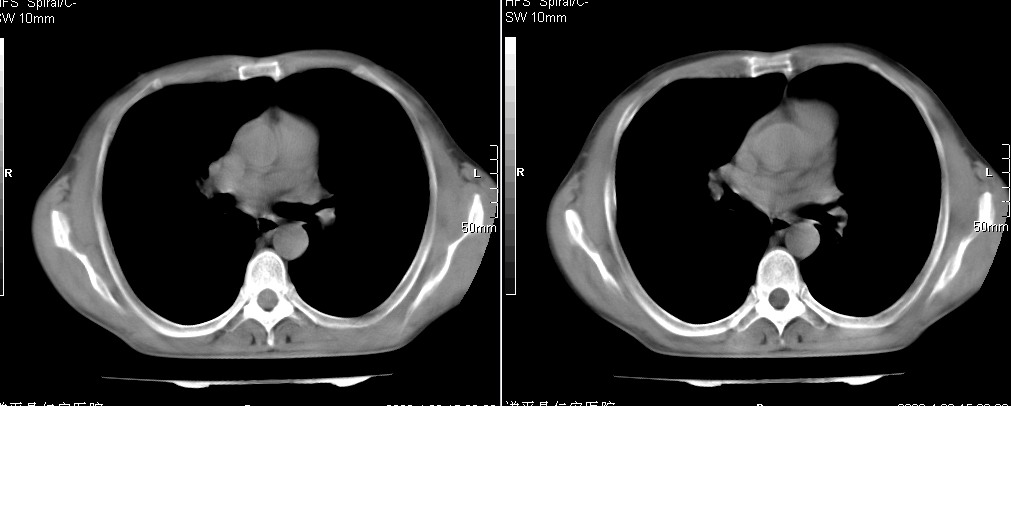

以下是引用yangyudong333在2008-4-27 16:58:00的发言:[br]病灶无明显分叶,周围有粗大索条影,外侧与胸膜接触面较宽且胸膜下透亮层存在,内部可见充气支气管,考虑炎症可能性大,建议抗炎治疗后复查

以下是引用mzh123在2008-4-27 19:30:00的发言:[br]右肺中叶团片致密影,周围可见卫星病灶,中叶支气管未见明显狭窄,所以首先考虑炎性病变,结核可能性大,肺癌待排,请治疗后复查!

以下是引用随光逐影在2008-4-27 20:49:00的发言:[br]考虑为:1)右肺中叶及左侧下叶感染性病变。2)左肺下叶支气管扩张?建议:抗炎治疗后复查。